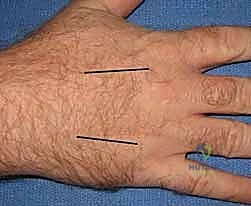

Decompression of the hand requires releasing the interosseous, thenar, and hypothenar compartments. Two longitudinal dorsal incisions are typically utilized: one centered over the second metacarpal (to access the first and second dorsal interossei) and one over the fourth metacarpal (to access the third and fourth dorsal interossei).

Blunt dissection is carried down alongside the metacarpal shafts to decompress the volar interossei and the adductor pollicis. The thenar and hypothenar compartments can be decompressed via separate small longitudinal incisions on the radial and ulnar borders of the hand, respectively.

For the digits, mid-axial incisions are placed on the non-contact borders (ulnar border of the index and middle fingers; radial border of the ring and small fingers).

The incision is carried down through the skin and subcutaneous tissue.

The dissection must divide Cleland's and Grayson's ligaments to fully decompress the digital compartments while carefully protecting the neurovascular bundles lying volar to the mid-axial line.